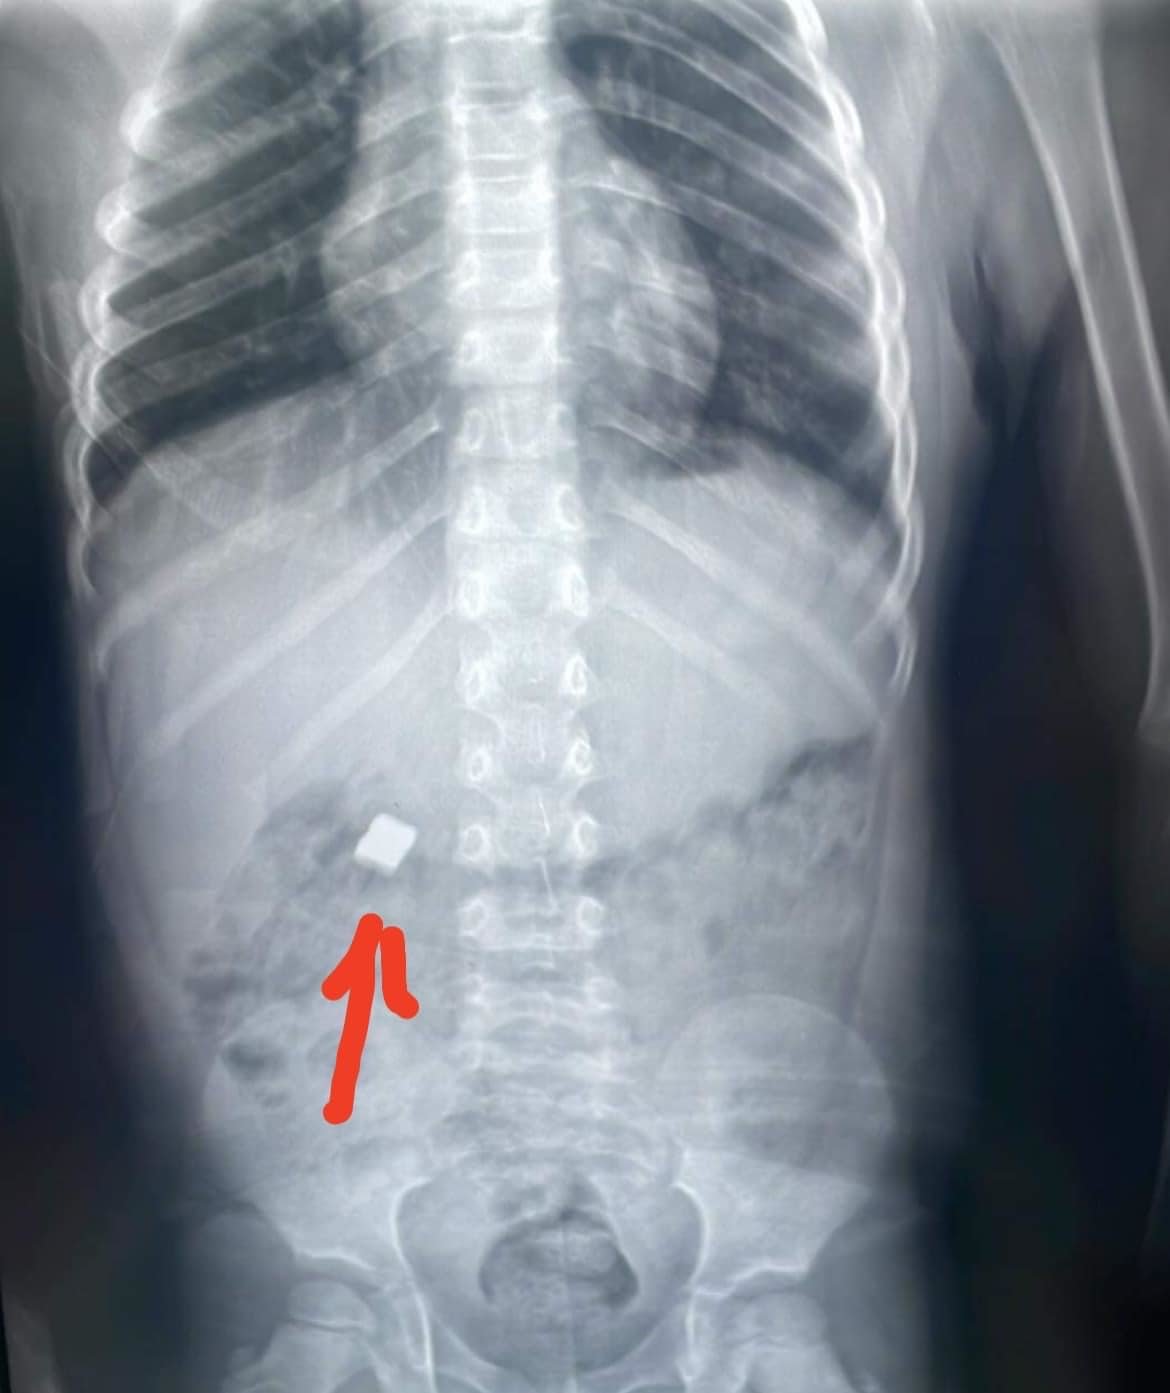

Жил бүрийн шинэ жилийн баярыг тохиолдуулан хүүхдэд зориулсан төрөл бүрийн бэлэг худалдаалж эхэлдэг. Уг бэлгэнд ихэвчлэн чихэр амттан, хүүхдийн янз бүрийн тоглоом зэрэг багтдаг. Энэхүү тоглоомонд хийдэг товчин зайг хүүхдүүд залгих эрсдэлтэй байгааг гарч байгаатай холбоотой ЭХЭМҮТ-өөс анхааруулга өглөө.

Тодруулбал, ЭХЭМҮТ-өөс "Эцэг, эхчүүдийн анхааралд! Хүүхдийн шинэ жилийн бэлгэн дотор товчин зайтай чихэр, тоглоом ихээр худалдаалагдаж, хүүхэд эрүүл мэндээрээ хохирох эрсдэл их байна. Тиймээс ийм төрлийн бэлгийг хүүхэддээ битгий бэлэглээрэй. Чихэргүй шинэ жил хийцгээе." хэмээн уриалж байна.